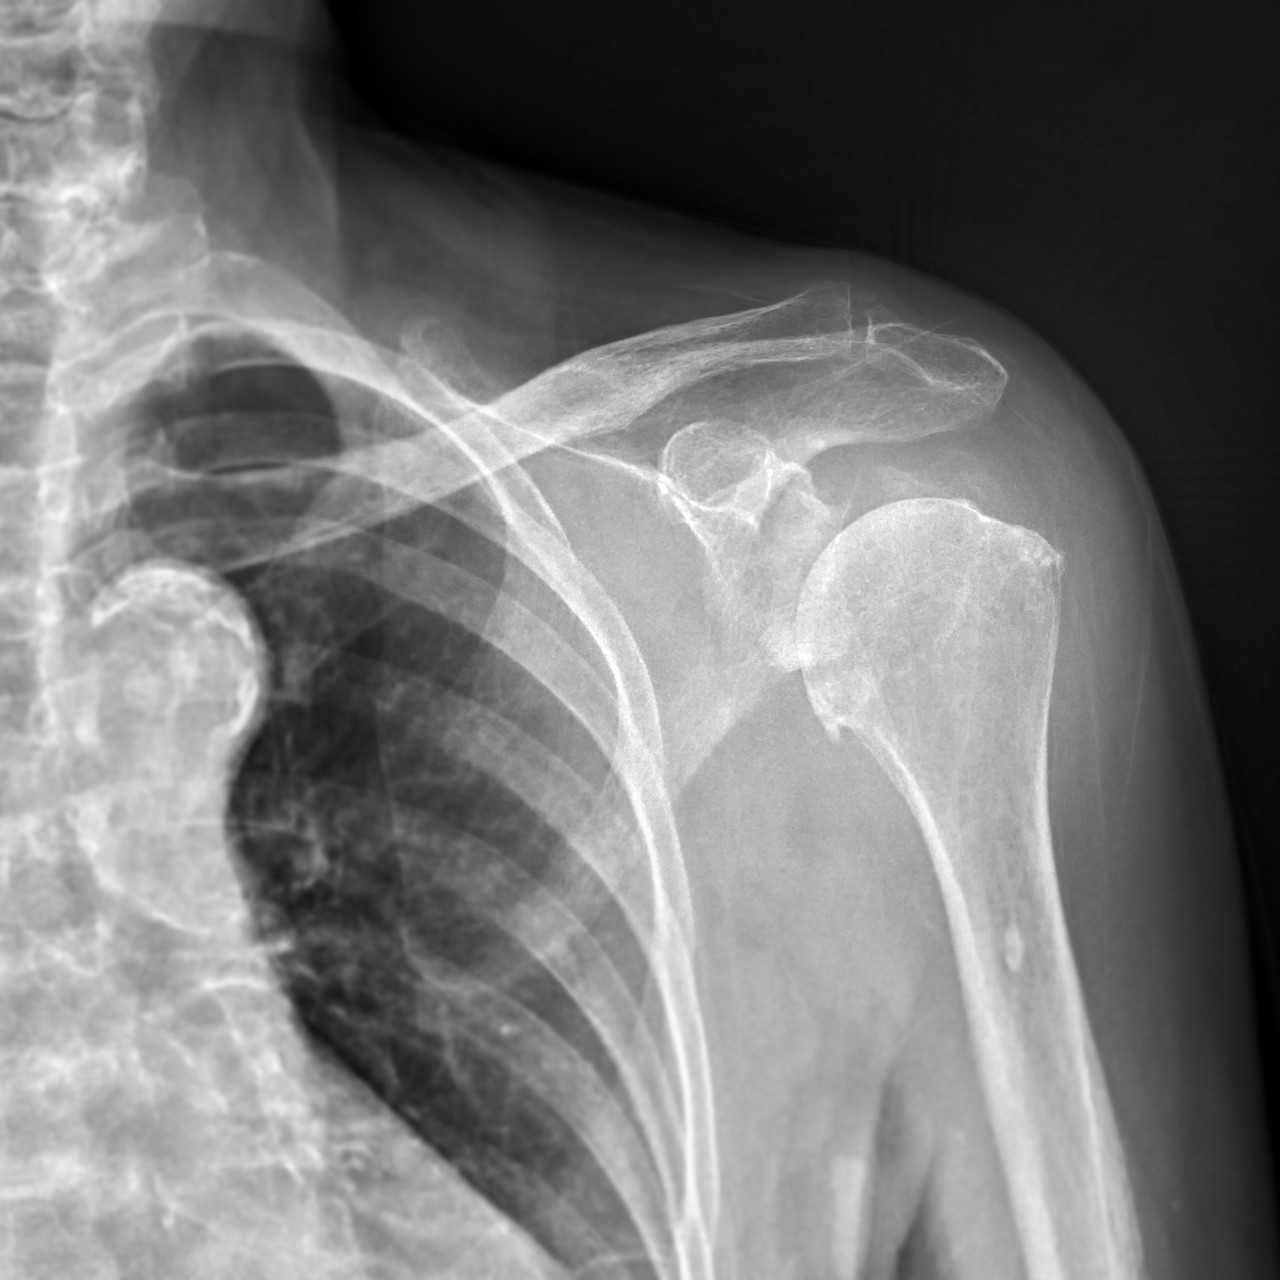

SHOULDER IMPINGEMENT

충돌증후군

충돌증후군은 이런 구조물들이 퇴행성 변화나 외상 등으로

인해 어깨를 위로 올리는 근육이 지나가는 길이 좁아지면서

주변의 뼈나 인대에 충돌하여 통증이 발생하고, 심한 경우

근육이 뜯어지는 현상을 말합니다.

원장님과 상담 후 X-ray, 초음파 등 정밀 장비를 이용하여 정확하게 분석한 후 해당 결과를 토대로 재상담을 진행